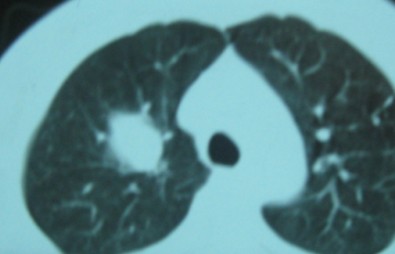

标题: CT192450:男37,自觉胸闷两月余 [打印本页]

标题: CT192450:男37,自觉胸闷两月余

右肺上叶良性肿瘤---错构瘤/硬化性血管瘤/炎性假瘤等。

考虑血管源性肿瘤,硬化性血管瘤可能性大;

不除外错构瘤。

考虑右肺上叶良性肿瘤(硬化性血管瘤?炎性假瘤?)。

边缘有毛刺,考虑癌

右肺上叶良性新生物---炎性假瘤或结核球/错构瘤/硬化性血管瘤等